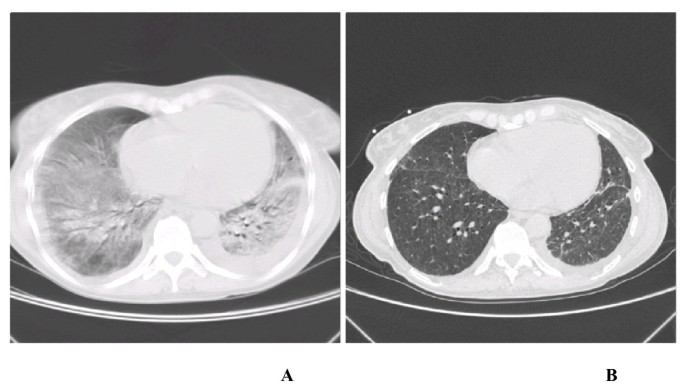

A 44-year old white woman was admitted to our hospital complaining of dyspnoea, non-productive cough and 40°C fever for the past 2 days. She had been diagnosed with SLE at the age of 18 years. The course of her SLE was well controlled in an outpatient clinic. She had never smoked. On examination on admission she was febrile, with tachycardia (HR 100/min) and tachypnoe 24/min. On auscultation loud crackles were audible over the both lungs. Chest X-ray revealed an interstitial pattern with bilateral ground-glass shadow. Her WBC was 11.4 × 103/μl, C-reactive protein 198 mg/l, sedimentation rate 90 mm after 1 hour. Blood gases measurement in the arterialized blood from the capillary vessels revealed severe respiratory failure with hypoxaemia (pO2 39.4 mmHg, pCO2 30.5 mmHg, Sat 75.5%). An atypical pneumonia was suspected. Intravenous antibiotics (ciprofloxacin and spiramicin), oxygen (2 l/min) and steroids (methylprednisolone in the dose 1 mg/1 kg of the body mass orally) were started. Repeated blood gases evaluations showed no improvement thus the rate of oxygen flow was increased to 4 l/min and methylprednisolone to 0.5 g daily intravenously. After 2 days of such treatment a significant improvement was observed. She was afebrile, with HR 70/min, respiratory rate 16/min, pO2 64.0 mmHg, pCO2 28.4 mmHg, Sat 93.1%. On the 3rd day after admittion patient's condition suddenly deteriorated with severe dyspnoe, fever (39°C), shivers, HR 130 – 150/min and respiratory rate 45/min. She has been transferred to the ICU, required endotracheal intubation and mechanical ventilation. High resolution computed tomography (HRCT) showed ground glass opacity (Figure. 1A.). There were negative repeated sputum and blood cultures. Bronchoalveolar lavage (BAL) cultures were also negative.

The past medical history included symptoms of respiratory tract infection, arthralgia, oral ulcers, fever and skin rush noted in November 2004. Anti-nuclear antibodies (ANA) level was 1:1280 (range: till 1:80). Patient was diagnosed in an immunology outpatient clinic as a recurrence of SLE and effective treatment with methotrexate, cyclosporin and methylprednisolone was introduced. For an unknown reason the treatment has been suddenly stopped and changed to monotherapy with chloroquine just 4 days before the development of symptoms and admission to our hospital. The level of pANA was 1:2560. Taking this and negative sputum and blood cultures into consideration we diagnosed fulminant lupus pneumonitis. Intensive immunosuppressive treatment has been introduced with pulses of cyclophosphamide (CP) (0.6 g iv/daily on the first day in the ICU, 0.4 g on the 2nd and 3rd days, 0.2 g for the next 4 days and with following 0.1 g iv and later orally), methylprednisolone (1 g iv/daily) (Figure. 2.) and mesna to prevent the urotoxicity of CP. The patient's condition gradually improved and she was extubated on the 5th day and transferred to the Pneumonology Department. A significant leukopenia as a side effect of the immunosuppressive agents was observed (drop in the WBC from 8.4 × 103/μl down to 1.5 × 103/μl during 4 days) (Figure. 2). Despite preventive antibiotic treatment (ceftriaxone 4 g iv/daily) 39°C fever developed. Antibiotics has been changed to levofloxacine (1 g iv daily) and amikacin (0.5 g iv daily) and patient felt better. Doses of cyclophosphamide previously reduced to 100 mg po daily had been withdrawn. Methylprednisolone was given orally 1 mg/kg of the body mass daily. The bone marrow biopsy has been performed showing intensive hematopoietic cells differentiation and maturation which has been mirrored in the peripheral blood count (increase in the WBC to 8.8 × 103/μl after 7 days without granulocyte colony-stimulating factor treatment). She was discharged 1 week later with HRCT confirmed significant remission of pulmonary changes (Figure. 1B.) and referred to follow up in an outpatient clinic.